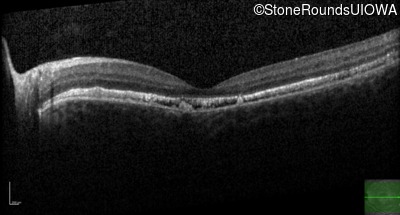

Age at visit: 17 years

This 15 year old girl came to medical attention during a routine athletic vision screening when the acuity in her right eye was observed to be abnormal.

Diagnosis & molecular findings

Best Disease BEST1 Asp228Glu GAC>GAG Asn259 ins2aacAA AR